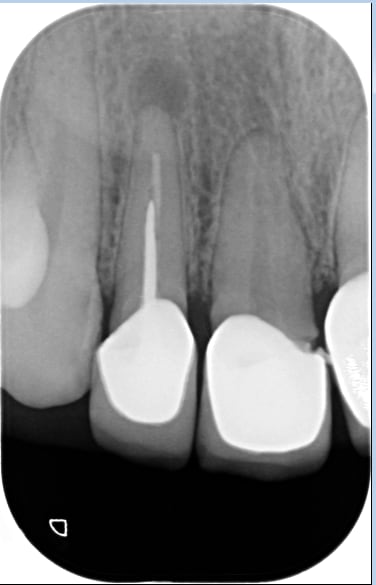

C'est une jeune femme qui a d'affreuses CCM faites il y a 8ans en surcontour gingival au niveau 12-11-21-22..

Ces CCM sont très volumineuses, débordant dans le sulcus avec une limite de préparation en congé hyperagressive et très sous gingivale... La patiente a un sourire gingival et on ne voit que cette gencive rouge violacée hypertrophiée..

J'ai déjà démonter 3 des 4 CCM, fait les traitements endo et j'ai posé les provisoires en retrait du congé pour aider à la cicatrisation ???

Le problème est qu'au bout de 2mois, je vois très peu d'amélioration de l'état gingival sur les 3 premières provisoires... Et mes provisoires sur 12, 11 et 21, en retrait du congé traumatique sont peu rétentives alors je m'inquiète pour les définitives en CCC..

T'as un cas galère, le rapport racine/couronne est flippant.